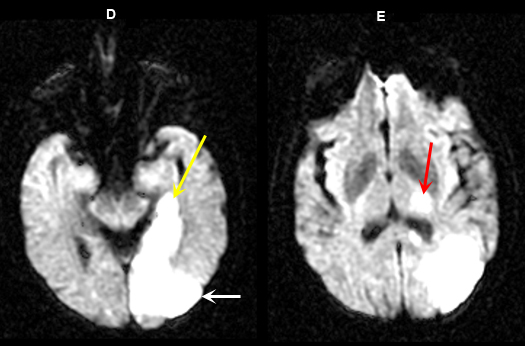

Figure 5 D-E: MR Images

|

Imaging findings: Figure 5 D-E (DW images)

Acute infarction involving the left occipital lobe (yellow arrow in Fig. A), adjacent left temporal lobe (white arrow in Fig. D) and infarction within the left thalamus (red arrow in Fig. E) is best appreciated on diffusion wtd. pulse sequences. |